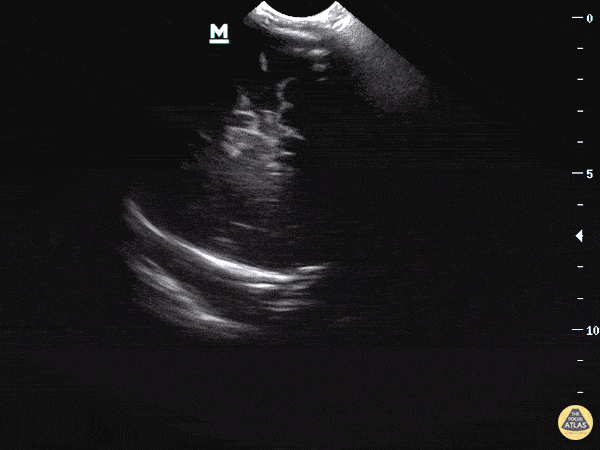

Clip 2: There is also asymmetry, specifically asymmetric ventricles with the left ventricle appearing larger than the right.